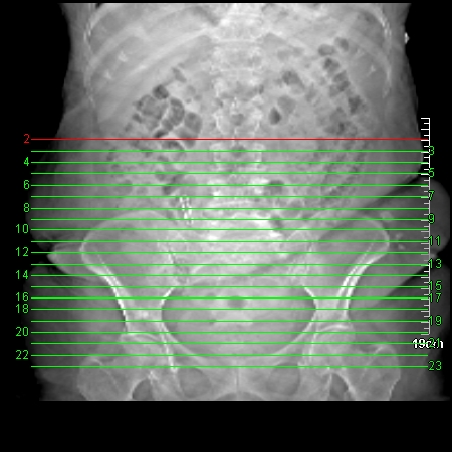

标题: CT10840: F/86 阑尾术后,B超发现腹部包块,强烈呼吁医疗安全 [打印本页]

标题: CT10840: F/86 阑尾术后,B超发现腹部包块,强烈呼吁医疗安全

术前的疏忽,手术前诊断阑尾炎,但是没有常规做b超,导致术后1周检查发现 1。实性包块?2。腹腔术后脓肿?

病史:病人一周前诊断阑尾炎,未做b超,手术发现阑尾化脓,(没有留意有无包块),术后1周病人发热,血象:1.6万,做b超发现,随ct检查,上传图片